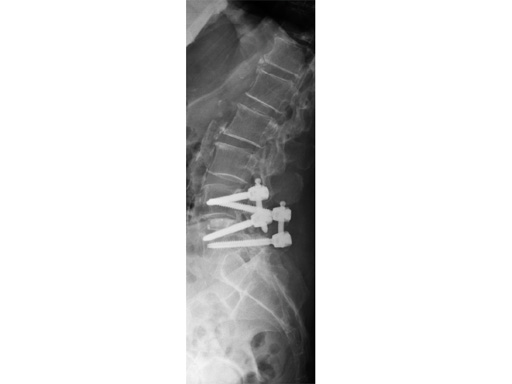

This system uses cannulated pedicle screws attached to screw-mounted tissue retractors. This combination allows pedicle screw insertion and rod introduction with minimal tissue disruption. The system is applicable to single and multi-level procedures requiring posterior instrumentation.

Unique to Matrix MIS are cannulated pedicle preparation instruments, screw-mounted tissue retractors and a rod introduction instrument.

Matrix MIS allows for minimally invasive rod and screw insertion during thoracolumbar pedicle fixation. Pedicle trauma is minimized by using muscle-sparing approaches to expose patient anatomy.